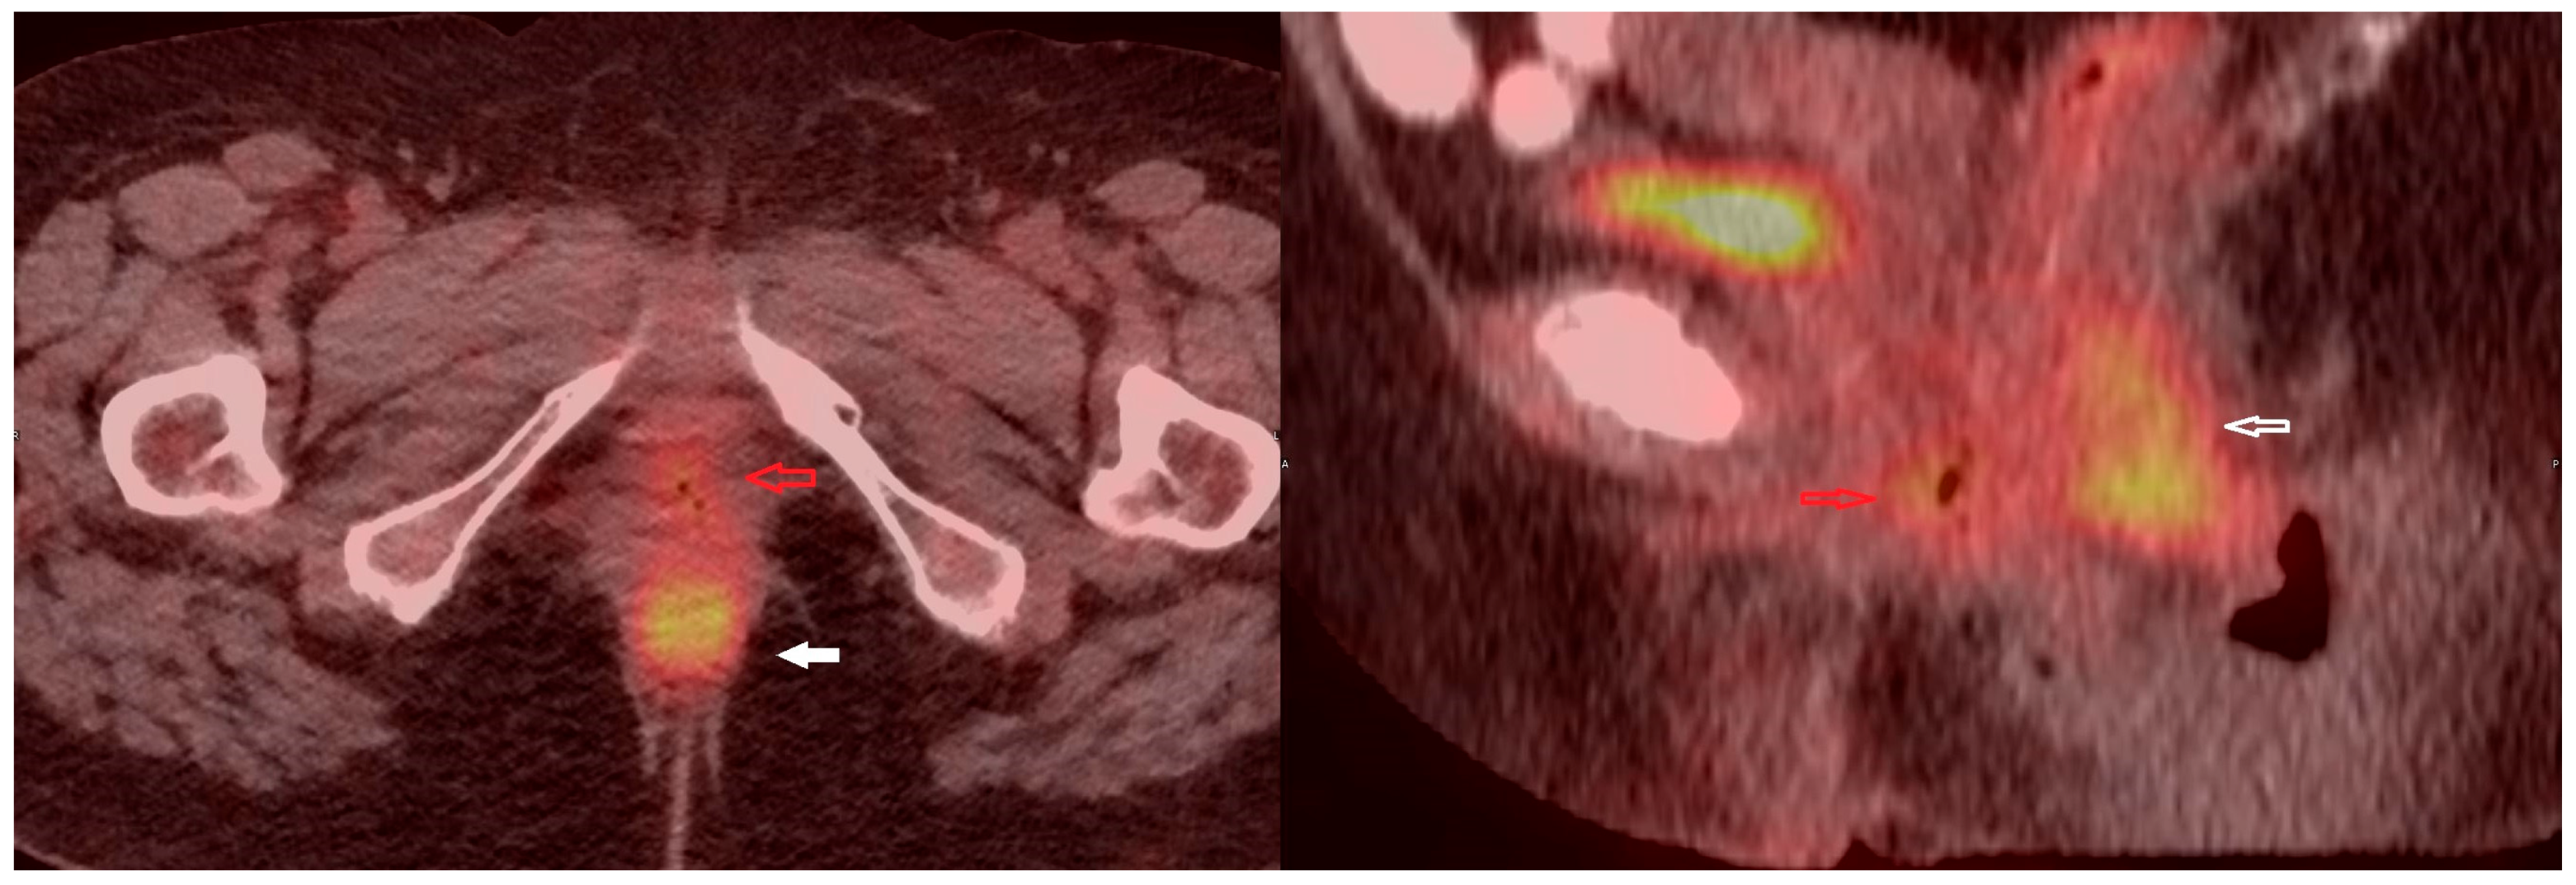

Primary Vaginal Mucinous Adenocarcinoma of Intestinal Type—Clinical, Radiological and Morphological Aspects

2. Case Presentation